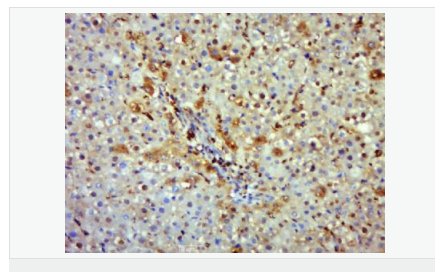

| 产品应用 | WB=1:500-2000 IHC-P=1:100-500 IHC-F=1:100-500 Flow-Cyt=1μg/Test ICC=1:100-500 IF=1:100-500 (石蜡切片需做抗原修复) not yet tested in other applications. optimal dilutions/concentrations should be determined by the end user. |

| 产品介绍 | Nitric oxide (NO) is an inorganic, gaseous free radical that carries a variety of messages between cells. Vasorelaxation, neurotransmission and cytotoxicity can all be potentiated through cellular response to NO. NO production is mediated by members of the nitric oxide synthase (NOS) family. NOS catalyzes the oxidization of L-arginine to produce L-citrulline and NO. Two constitutive isoforms, brain or neuronal NOS (b or nNOS, type I) & endothelial cell NOS (eNOS, type III), and one inducible isoform (iNOS, type II), have been cloned. All NOS isoforms contain calmodulin, nicotinamide adenine dinucleotide phosphate (NADPH), flavin adenine dinucleotide (FAD), and flavin mononucleotide (FMN) binding domains. Nitric oxide synthase is expressed in liver, macrophages, hepatocytes, synoviocytes, stimulated glial cells and smooth muscle cells. Cytokines such as interferon-gamma (IFN), tumor necrosis factor (TNF), interleukin-1 and -2, and lipopolysaccarides (LPS) cause an increase in iNOS mRNA, protein, and activity levels. Protein kinase C-stimulating agents exhibit the same effect on iNOS activity. After cytokine induction, iNOS exhibits a delayed activity response which is then followed by a significant increase in NO production over a long period of time. Human iNOS is regulated by calcium/calmodulin (in contrast with mouse NOS2). Function: Produces nitric oxide (NO) which is a messenger molecule with diverse functions throughout the body. In macrophages, NO mediates tumoricidal and bactericidal actions. Also has nitrosylase activity and mediates cysteine S-nitrosylation of cytoplasmic target proteins such COX2. Subunit: Homodimer. Binds SLC9A3R1. Tissue Specificity: Expressed in the liver, retina, bone cells and airway epithelial cells of the lung. Not expressed in the platelets. Similarity: Belongs to the NOS family. Contains 1 FAD-binding FR-type domain. Contains 1 flavodoxin-like domain. SWISS: P35228 Gene ID: 4843 Database links: Entrez Gene: 4843 Human Entrez Gene: 18126 Mouse Omim: 163730 Human SwissProt: P35228 Human SwissProt: P29477 Mouse Unigene: 709191 Human Unigene: 2893 Mouse Unigene: 10400 Rat Important Note: This product as supplied is intended for research use only, not for use in human, therapeutic or diagnostic applications. 合成与降解(Synthesis and Degradation) 催化生物体内一氧化氮(NO)生成的酶。分神经型一氧化氮合成的酶(nNOS or NOS-1)、诱导型一氧化氮合成的酶(iNOS or NOS-2)、内皮型一氧化氮合成的酶(eNOS or NOS-3)。 |